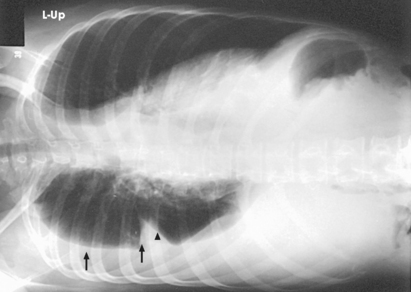

Structures shown: AP or PA projection obtained using the lateral decubitus position shows the change in fluid position and reveals any previously obscured pulmonary areas or, in the case of suspected pneumothorax, the presence of any free air (Figs. 10-62 to 10-64).

Fig. 10-62 AP projection, right lateral decubitus position, showing a fluid level (arrows) on the side that is down. Note the fluid in the lung fissure (arrowhead). Note correct marker placement, with the upper side of the patient indicated.

Fig. 10-63 AP projection, left lateral decubitus position, in same patient as in Fig. 10-64. Arrows indicate air-fluid level (air on the side up). Note correct marker placement, with upper side of the patient indicated.